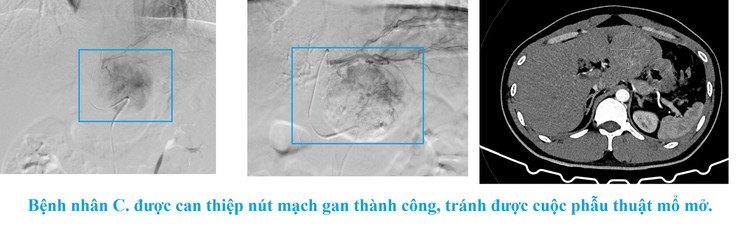

Nhờ phát hiện sớm - chẩn đoán chính xác - xử trí kịp thời, bệnh nhân Nguyễn Văn C. đã được chuyển viện an toàn. Bệnh nhân C được thực hiện can thiệp nút mạch gan tại Bệnh viện Đa khoa tỉnh Quảng Ninh kịp thời, tránh được được cuộc phẫu thuật mổ mở. Hiện tại, sức khỏe ổn định.

Bệnh nhân được các bác sĩ tiến hành khám và chỉ định thực hiện các xét nghiệm cần thiết như siêu âm, chụp CT-scanner ổ bụng. Kết quả siêu âm cho thấy có khối u ở gan trái, kích thước 56x58mm, bờ mất liên tục, có tụ dịch dạng máu ở mặt trước dạ dày và dịch ổ bụng 50mm.

Đây là hình ảnh khối u gan trái đang chảy máu trong bao gan, có nguy cơ vỡ gan, gây mất máu cấp, đe dọa tính mạng bệnh nhân bất cứ lúc nào.